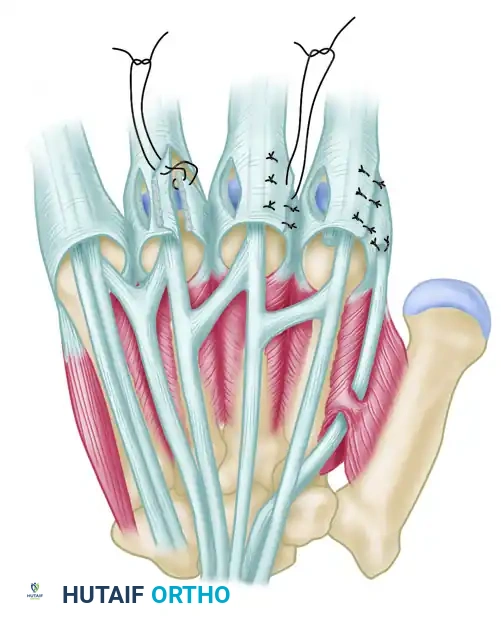

4. Extensor Mechanism Centralization

To correct the ulnar drift, the extensor tendon must be centralized and secured.

* Ulnar Relaxing Incision: Make a secondary longitudinal incision on the ulnar side of the central tendon. This acts as a relaxing incision, freeing the tethered extensor mechanism and permitting it to be repositioned dorsally over the metacarpal head. This ulnar incision is left open to heal by secondary intention.

* Radial Imbrication: Realign the extensor tendon directly over the MCP joint. Close the radial-sided incision in the extensor hood using nonabsorbable sutures (e.g., 4-0 braided polyester or nylon). The edges of the radial hood should be overlapped (imbricated) to tighten the radial sagittal band and securely hold the tendon in its centralized position.

Figure 73-23 (Parts 3 & 4): The incision on the radial side of the hood is closed after its edges are overlapped (imbricated) to maintain the centralized position of the extensor tendon.

The Flatt Transfer

The Flatt transfer involves releasing the deforming ulnar intrinsic insertions and transferring them to the radial side of the adjacent digits to provide a corrective radial pull.

- Ulnar Release: Through the existing exposure, identify the ulnar intrinsic tendon insertion on the ulnar side of the central tendon. Make an incision to release this insertion completely.

- Mobilization: Free the ulnar intrinsic insertion from its surrounding adhesions.

- Transfer: Reroute the released ulnar intrinsic tendon and suture it to the capsule or the radial collateral ligament on the radial side of the MCP joint of the adjacent ulnar finger.

Figure 73-24: The Flatt transfer of released ulnar intrinsics to the radial side of adjacent digits. The ulnar intrinsic insertion is freed and sutured to the radial capsule of the adjacent finger to counteract ulnar drift.